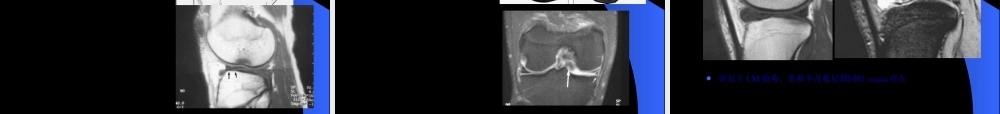

MRIMRI在膝关节创伤在膝关节创伤(chuāngshāng)(chuāngshāng)的应用的应用第一页,共六十四页。第一页,共六十四页。膝关节创伤的MRI半月板病变韧带(rèndài)病变软骨病变其它第二页,共六十四页。第二页,共六十四页。半月板-解剖纤维软骨结构LM:类圆形(O),前后部分(bùfen)相对等宽–外周疏松连接,外后腘肌腱和鞘与关节囊分开–半月板股骨韧带MM:半圆形(C),后部比前部宽–外周与关节囊紧密连接10MM10MM3LM3LM2ACL2ACL8PCL8PCL第三页,共六十四页。第三页,共六十四页。横韧带连接2个半月板前角位置(wèizhi):–关节囊之前–Hoffa’s髌下脂肪后部出现率:矢状面64%厚度:可变11横韧带横韧带22和和33半月板股骨半月板股骨(gǔgǔ)(gǔgǔ)韧韧带带((HumphreyandWrisbergHumphreyandWrisberg韧带)韧带)44腘肌腱腘肌腱55和和6ACL,PCL6ACL,PCL第四页,共六十四页。第四页,共六十四页。半月板股骨韧带LM后角—股骨内髁–Humphrey韧带(rèndài):PCL之前–Wrisberg韧带:PCL之后–出现率单个出现>1/3以上同时出现率6-20%第五页,共六十四页。第五页,共六十四页。半月板-技术考虑矢状位和冠状位短TE图像(túxiànɡ)优于长TE图像(túxiànɡ)-T1WI,PDWI,GRE优于T2WI第六页,共六十四页。第六页,共六十四页。正常半月板断层表现第七页,共六十四页。第七页,共六十四页。半月板撕裂诊断标准信号异常:信号异常:Grade0:Grade0:纤维软骨纤维软骨(ruǎngǔ)(ruǎngǔ)结构,所有序结构,所有序列上低信号列上低信号Grade2:Grade2:变性变性Grade3:Grade3:半月板撕裂半月板撕裂第八页,共六十四页。第八页,共六十四页。半月板撕裂-Grade3信号第九页,共六十四页。第九页,共六十四页。半月板-Grade2信号可以(kěyǐ)演变为撕裂第十页,共六十四页。第十页,共六十四页。半月板撕裂-形态异常游离(yóulí)缘变钝小的三角形破碎消失领结中断局限性凹陷后角小于前角外侧半月板前角高度>6mm第十一页,共六十四页。第十一页,共六十四页。半月板撕裂诊断标准同时考虑(kǎolǜ)信号和形态的改变第十二页,共六十四页。第十二页,共六十四页。半月板特殊信号异常半月板内撕裂(sīliè)或囊肿第十三页,共六十四页。第十三页,共六十四页。半月板撕裂分类层裂斜裂纵裂(zònɡliè)放射状撕裂注注:MR:MR的作用的作用(zuòyòng)(zuòyòng)在于明确有无撕裂,对撕裂的分型能在于明确有无...